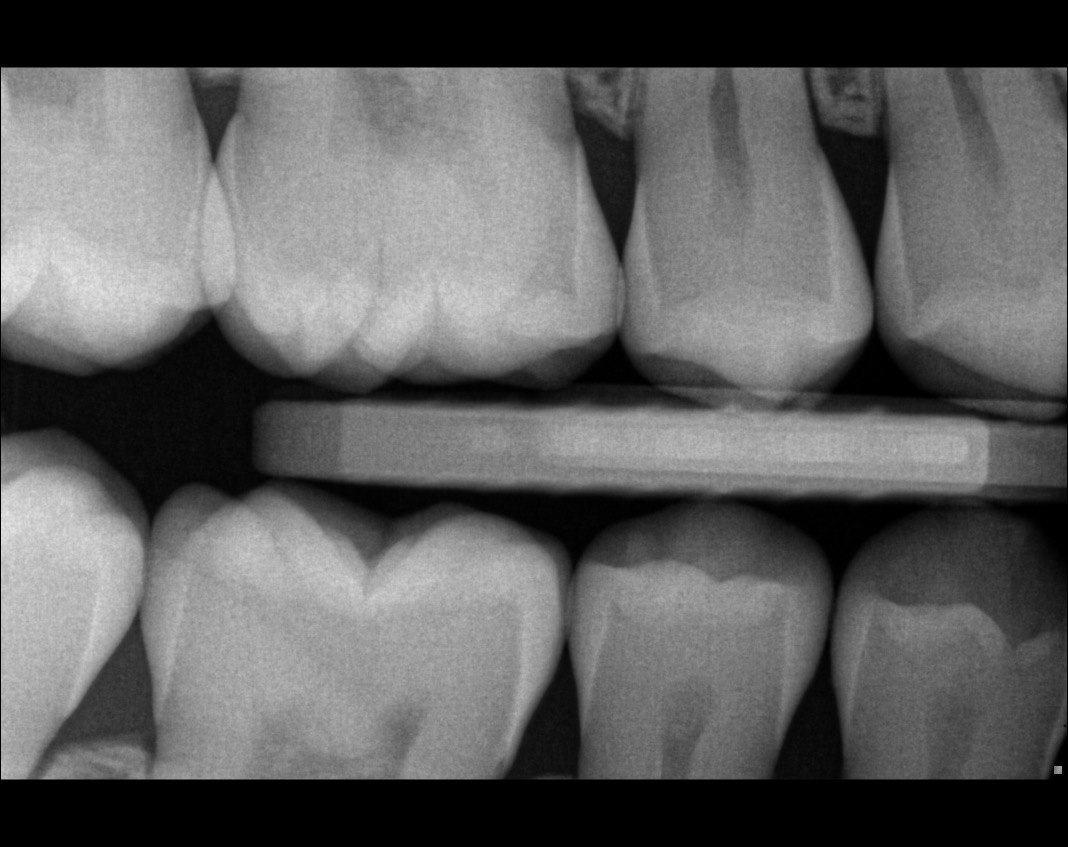

Question 22: What codition cannot be seen in the lower teeth in this X ray?

Question 24: Which condition can be detected in the following X ray?

Question 30: What option can be seen on the lower jaw of the following X ray?

Question 31: Which options can be selected for the following X ray?

Question 32: Which surface need restoration?